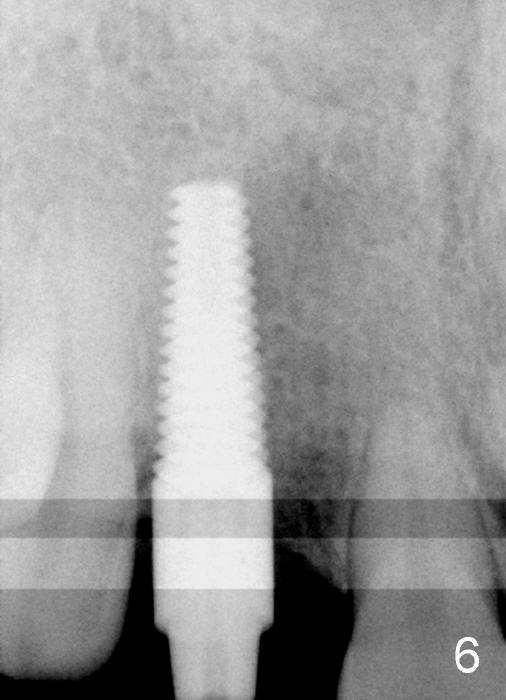

Malpositioned implant in the anterior region is cosmetically unacceptable. Immediate provisional allows us to note the issue immediately. The crown looks too long. Secondly, the provisional is easily dislodged, since the buccal aspect of the angled abutment is over trimmed (Fig.1). The implant (3.8x14 mm), which has been placed 3.5 months, is unexpectedly easily removed by reverse torque (Fig.2). The buccal wall is intact, whereas there seems to be enough bone lingually to place an implant. A small incision is made (Fig.11) so that the gingival tissue can be transferred buccally (Fig.12) and the immediate implant is to be placed palatally (Fig.13 white circle). There is no difficulty forming osteotomy in the palatal wall, followed by inserting 4.5x20 mm tap at the depth of 17 mm (Fig.3,5). But the tap is not palatal enough (Fig.4). By removing more palatal bone, the 4.5x17 implant (Fig.6) appears to be placed palatally enough for restoration (Fig.7; A: abutment; *: buccal gap). The biggest problem is that the palatal flap (Fig.7 arrowheads) cannot be pushed buccally; instead remains palatally. This leads to buccal tissue deficiency (Fig.8). Connective tissue graft is offered, but declined. The patient insists that she has low smile line. Following immediate provisional, mixture of allograft and synthetic graft is placed in the buccal gap (Fig.9). The overbuilt graft is held in place by perio dressing.